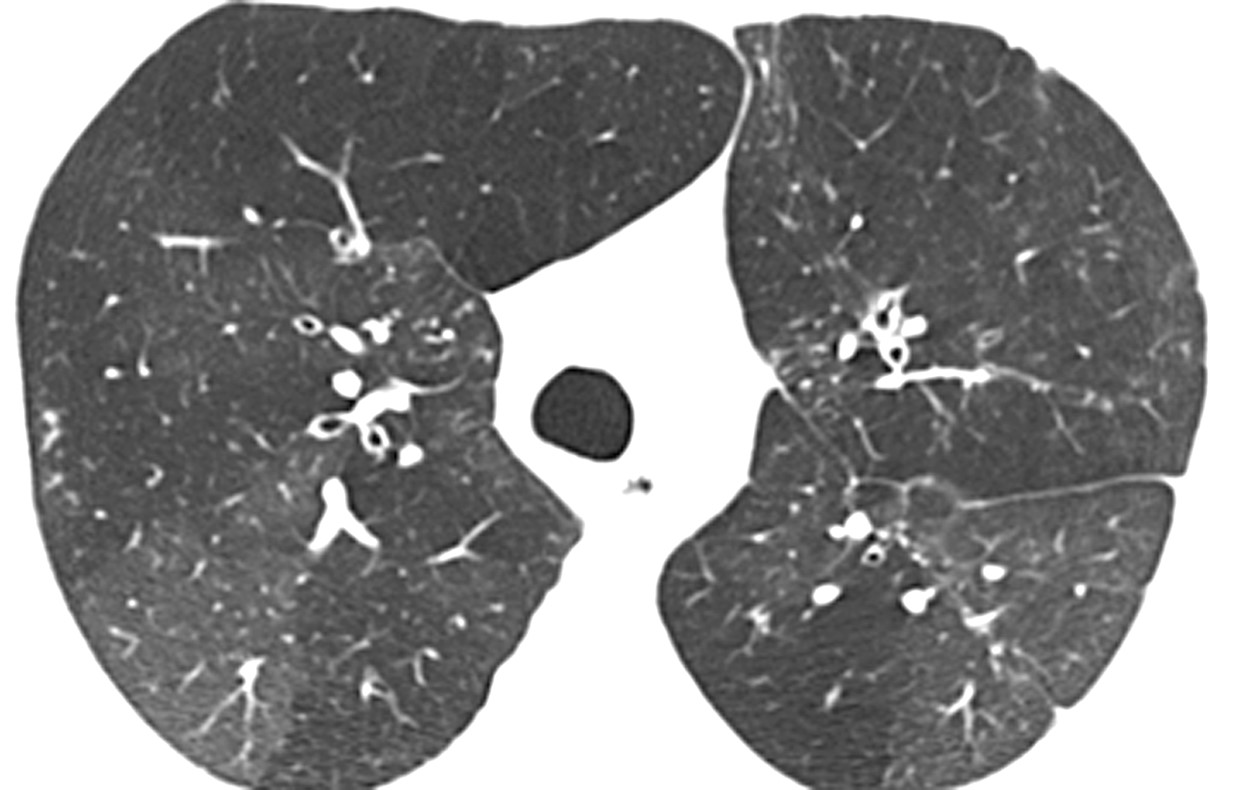

UIP: Example

UIP shows:3,6

- Subpleural and basal predominant distribution

- Honeycombing

- Traction bronchiectasis

The distribution of UIP is characteristically basal and peripheral, though often patchy.1,3,5,6

Image courtesy of and used with permission from Robert Suh, MD.

Honeycombing is critical for an HRCT diagnosis of UIP without surgical biopsy.1,3,5-7

In cases of UIP, ground-glass opacities (GGO) may be present but should be less extensive than the reticulation.1,3,6 Mediastinal lymphadenopathy may be present.3